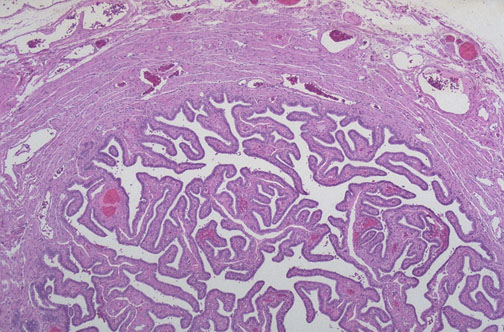

| Normal adult fallopian tube has a thin outer smooth muscular coat composed of ill-defined inner circular and outer longitudinal layers, and an inner complex branching pattern of finger-like projections of connective tissue lined by epithelial cells seen here at low magnification. The fallopian tubes conduct spermatozoa upward and ova downward to the endometrial cavity |